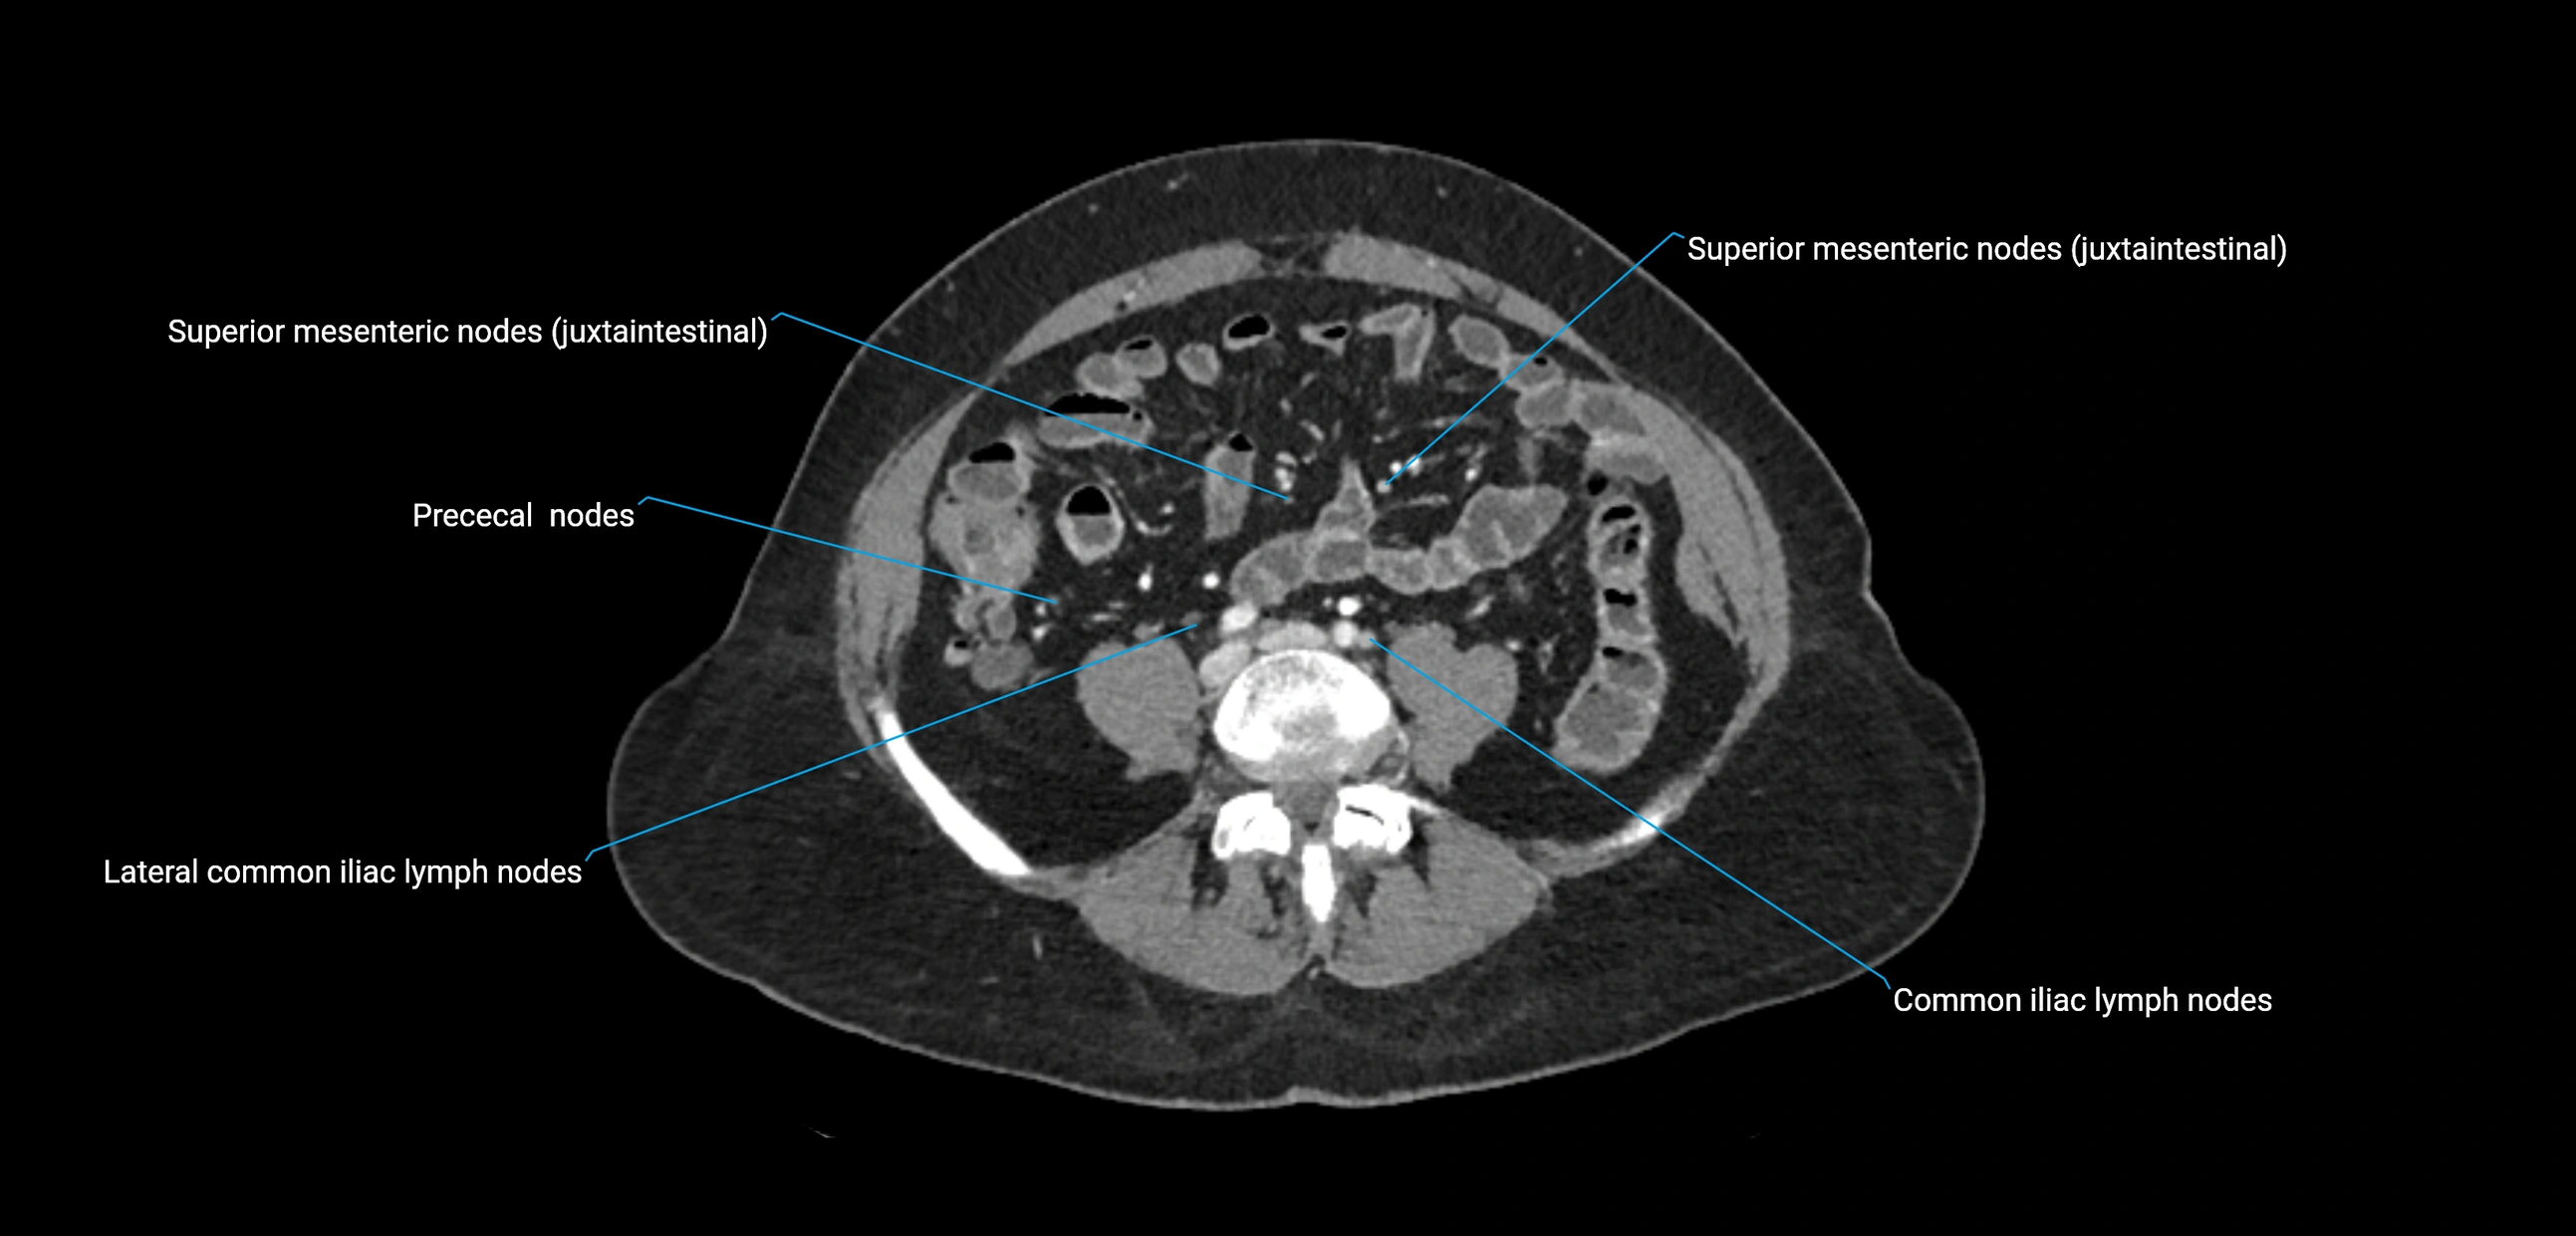

CT Appearance

CT Pre-Contrast:

• Nodes appear as soft-tissue density nodules adjacent to the aorta and IVC

• Calcification may be seen in chronic infections (e.g., tuberculosis)

CT Post-Contrast:

• Normal nodes enhance homogeneously

• Malignant nodes may show heterogeneous enhancement, central necrosis, or conglomerate formation

• Size >1 cm short axis is suspicious, though morphology and distribution are equally important

CT Venography (CTV):

• Demonstrates nodal encasement or compression of adjacent vessels (aorta, IVC, renal veins)

• Useful in staging testicular and ovarian malignancies

• Provides 3D reconstructions for retroperitoneal lymph node dissection planning